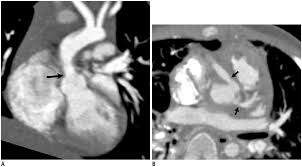

Supravalvular Aortic Stenosis Williams Syndrome Cardiac Case Studies Ctisus Ct Scanning

Computerized Tomography Use In Williams Beuren Syndrome Aortopathy Kalis Nn Sulaibikh Lk Al Amer Sr Al Amer Hy Heart Views

Contrast Enhanced Cardiac Computed Tomography Demonstrating Findings Of Download Scientific Diagram